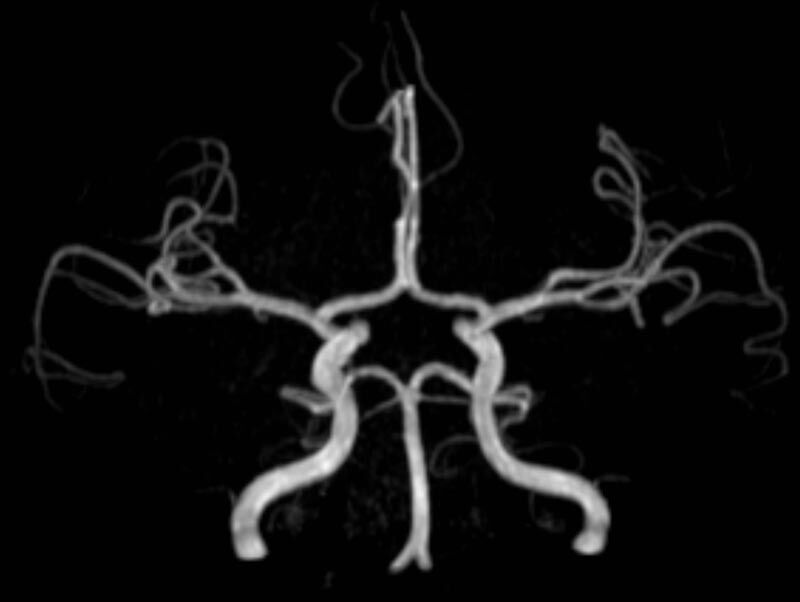

• intrakranielle Gefäße (Abklärung Verschluss, Stenose, Aneurysma)

• Halsgefäße zur Therapieplanung (z.B. Stent, Operation)

MR-Angiografie (MRA)

• MR-Angiografie ohne Kontrastmittel

• Time of Flight (TOF)-Angiographie

Je nach Fragestellung und Körperregion Gefäßdarstellung ohne Kontrastmittel bei Kontrastmittelunverträglichkeit oder terminaler Niereninsuffizienz möglich.

• MR-Angiographie mit Kontrastmittel

• Erfassung arterieller und venöser Gefäße/Bypässe aller Körperregionen mit 3D-Rekonstruktion